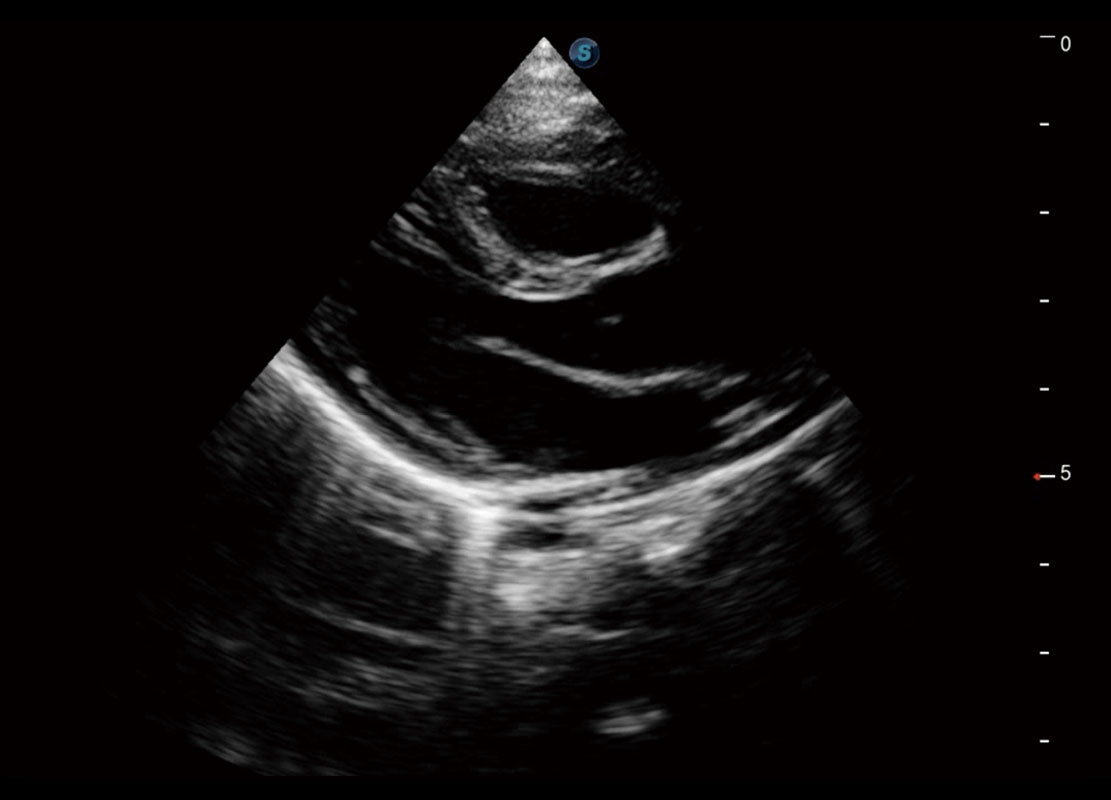

P60搭载宽频带线阵探头、宽景成像、弹性成像技术,为您提供乳腺应用方案。P60支持高频相控阵探头、线阵探头、腹部高频探头、腹部微凸探头等,丰富的探头群搭载敏感的彩色血流成像,适用于新生儿多种脏器检测要求,满足新生儿筛查需求。

新生儿肝血管癌

新生儿脊髓圆锥

新生儿心脏